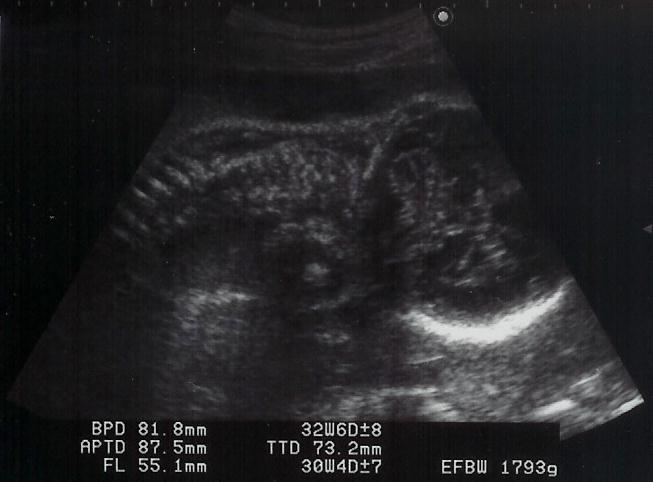

|  shigeru、3週間ぶりの健診です。ママは後期の検査がありました。ここのところ、ママは夜眠れない日々が続いています。そのことをお医者様に話したら・・・「(shigeru)重さは1793g。重くなったんだもの、眠れないのは仕方ないですよ。」と。ママは眠いときに眠れば、夜に眠れなくても大丈夫とのこと。お医者様は「かわいいわね〜」とエコーをみながら言いましたが、ママには骸骨か宇宙人にしかみえません。でも、shigeruは大きくなりましたね。ほっぺがふっくらしているのがエコーでもわかるのですから。

右が頭で足を抱えて下を向いてます。

顔面アップ。右が頭で、こちらを向いています。